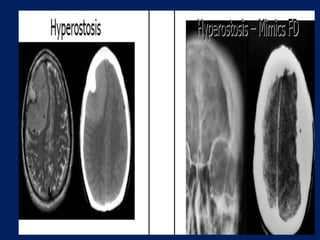

Meningiomas often induce an osteoblastic reaction in the adjacent

bone, resulting in a characteristic focal hyperostosis. They are also

hypervascular, receiving their blood supply predominantly from

dural vessels.

– Bone Changes

(Hyperostosis)